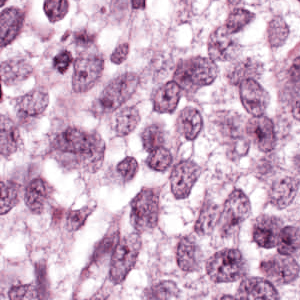

As an essential part of digital pathology, histopathology image analysis is playing increasingly important role in cancer diagnosis, which can provide direct and reliable evidence to diagnose the grade and type of cancer. This paper deals with nuclei segmentation, an important step in histopathological image analysis. The purpose of nuclei semgentation is not only counting the number of nuclei but also obtaining the detailed information of each nucleus. So unlike nuclei detection, here the outputs are the contour of each nucleus instead of only the position of their central points. Hence we can exactly extract each nucleus from the image and make it available for further analysis. For example, the features of the individual nucleus and the distribution of nuclei clusters can be used to grade and classify status of breast cancers [3, 4]. Because of appearance variation such as color, shape, and texture, nuclei segmentation from histopathological images could be very challenging, as illustrated in Fig.1, in which it is very challenging even for human to recognize and segment all nuclei within the images. Fig.1(a) and Fig.1(b) illustrate two histopathological images from different organs. Fig.1(c) and Fig.1(d) are two histopathological images from same organ but have different cancer grade.

Figure 1: (a)Colon cancer (b)Prostate cancer (c)Breast cancer (grade I) (d)Breast cancer(grade III)